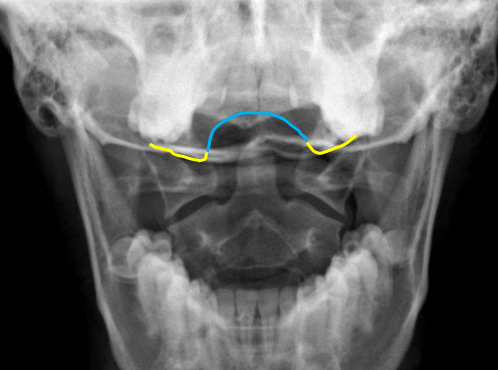

yellow

Occipital condyles

blue

Foramen magnum